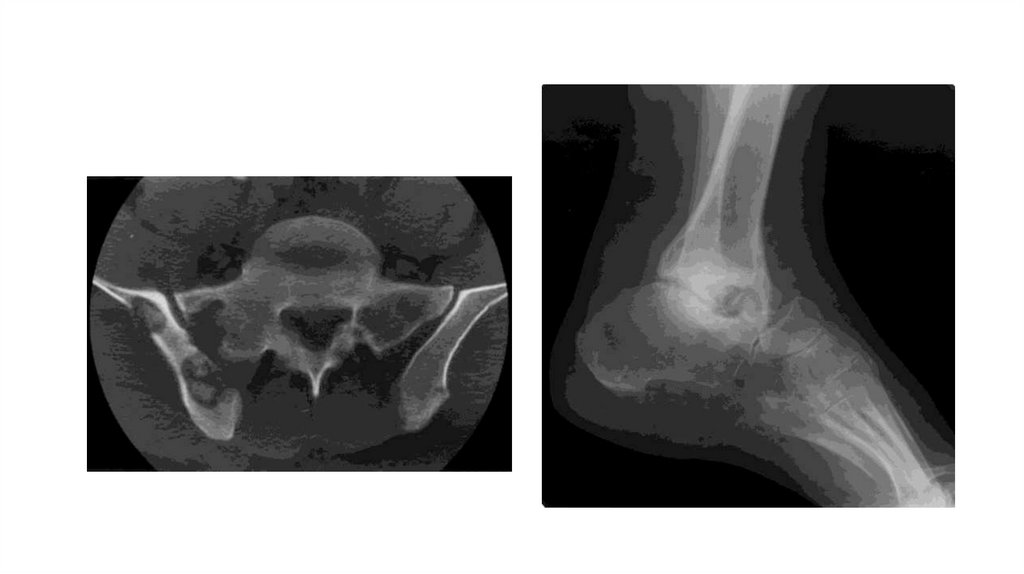

«Воспалительные

заболевания опорнодвигательного аппарата»